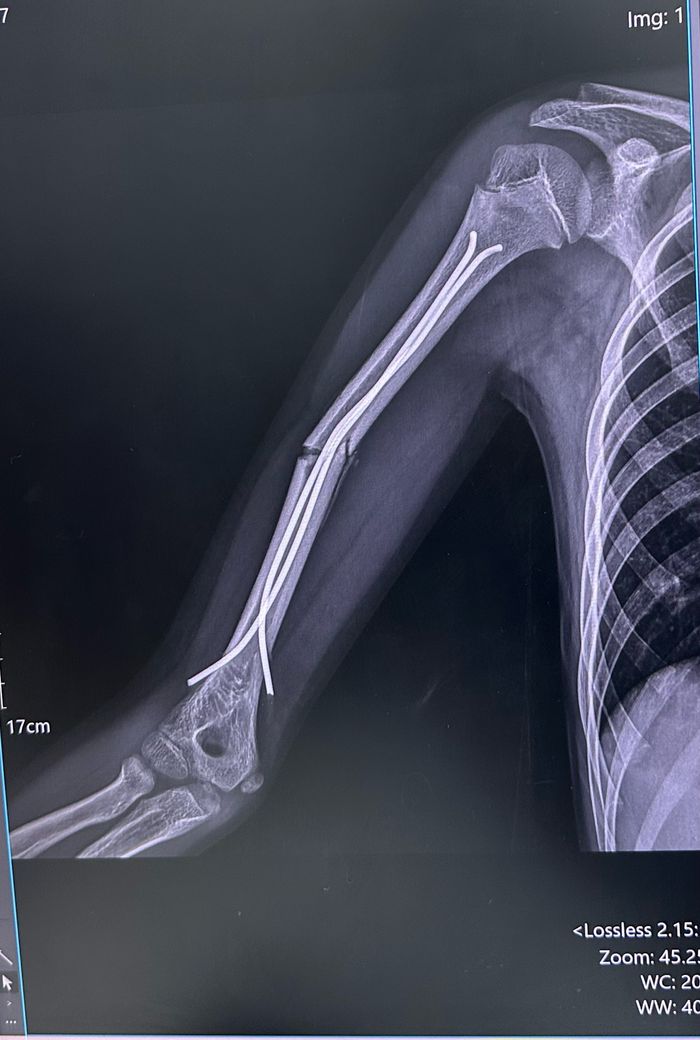

상완골 골절 핀삽입 후 금속판 재수술 필요한가요

핀고정술 잘붙었었는데 한주만에 이렇게 휘었다고

재수술을 하라고 하셔서요ㅠㅠ

핀이 이렇게 휘었다는것도 속상하고

아드님이 수술하신다니 걱정이 많이 되실 것 같습니다. 사진상 금속 핀이 휘어진 상태로 뼈의 정렬이 틀어진 모습이 보여요. 아이는 회복력이 좋아서, 재수술 후엔 대부분 정상 기능으로 잘 회복합니다.